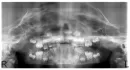

Моей дочери 7 лет. В 1,5 года у нее была сильная травма. Она упала и потеряла правый боковой резец с корнем. Был разрыв десны, а центральный правый резец был сильно травмирован, шатался, но через время прижился, чуть выше к десне. И вот травма сказывается. Настала смена зубов, левый центральный сменился, а правый не меняется, молочный (который прижился) не выпадает. Зачаток есть, но непонятно, вырастет или нет. Он стоит боком. Врачи не поймут, куда он повернут.

Есть ли на снимке постоянный боковой резец? Надо ли бить тревогу? Что делать? Куда обратиться?

Да, действительно зачаток резца есть.

Вероятность того, что он будет расти и прорезаться в таком положении, очень мала.

Вам нужно обратиться к врачу стоматологу-ортодонту. Возможно, ещё есть вероятность, вытянуть этот зуб с помощью брекет-системы и микроимплантов.